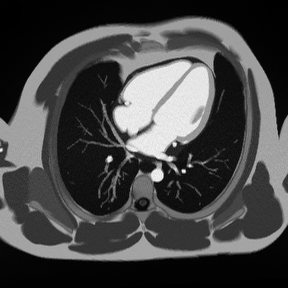

✅ Short-Axis Rest Perfusion Gradient Echo – Correct Image Example:

Short-Axis Rest Perfusion Gradient Echo – Correct Image Example

In the frame below, we can see a perfusion defect. This is the black semi-circle border that stretches the top-half of the left ventricle. (The left ventricle is shown on the right side in this image).

Cardiac perfusion defect showing transmural and subendocardial scar

To the right, we see that the damage only extends less than 50% through the heart wall, which indicates a sub-endocardial scar. There’s still viable myocardium that may yet recover.

But to the left, the damage stretches across the entire heart wall. This indicates a transmural scar, with no hope hope of recovery.

Things to Look for in Rest Perfusion:

• Dark areas that persist throughout contrast arrival indicate perfusion defects

• Normal myocardium should enhance uniformly within 1–2 heartbeats

• Subendocardial defects suggest microvascular disease

• Transmural defects indicate more severe disease or infarction